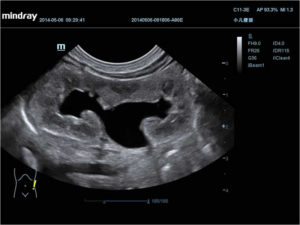

Нормальный размер почечной лоханки в 20 недель должен не превышать 5 мм, на третьем триместре 7 мм. Если уже после двадцатой недели лоханка расширяется больше чем на 10 мм, определенный объём жидкости начинает скопляться в почках, и развивается состояние под названием гидронефроз.

С развитием малыша увеличивается и сам орган, но при этом выведения мочи не происходит, а почечные лоханки под давлением жидкости увеличиваются еще больше. В конечном итоге, малыш рождается с многократно увеличенными органами и сразу после рождения, должен быть прооперирован.

Первичное расширение лоханки называется гидронефрозом. Он характеризуется затрудненным оттоком мочи, который вызывается патологическими процессами. Когда лоханка уменьшается в размере – это гипоплазия. В некоторых ситуациях лоханочные составляющие вообще могут отсутствовать.

Если жидкости в течение длительного времени много, эти части растягиваются. Поэтому врачи диагностируют гидронефроз у плода.

Степень расширения органов напрямую зависит от давления, образующегося в результате застоя. Стенки лоханки при этом заметно истончаются, постепенно возникает атрофия паренхимы почек. Это очень опасное состояние.

Стадии патологии

Под влиянием давления мочи осуществляется незначительное растяжение лоханки почки. На УЗИ врач замечает несколько увеличенный размер органа, однако его функционирование продолжается в обычном режиме. В этом случае нет причин для преждевременного волнения. Нет необходимости и в лечении.Давление на лоханки увеличивается, поэтому и размер всего органа тоже больший. Жидкость начинает давить на паренхиму, поэтому постепенно происходит ее атрофия. Функции органа плода явно нарушены. Возникает необходимость в дополнительном обследовании. Если женщина находится на третьем триместре беременности, возможен вариант вызывания преждевременных родов. Лечение новорожденного проходит более эффективно.Атрофия органа увеличивается. Функционирование почки фактически отсутствует. Постепенно фиксируется полное разрушение всего органа. Жизнь плода оказывается в большой опасности.